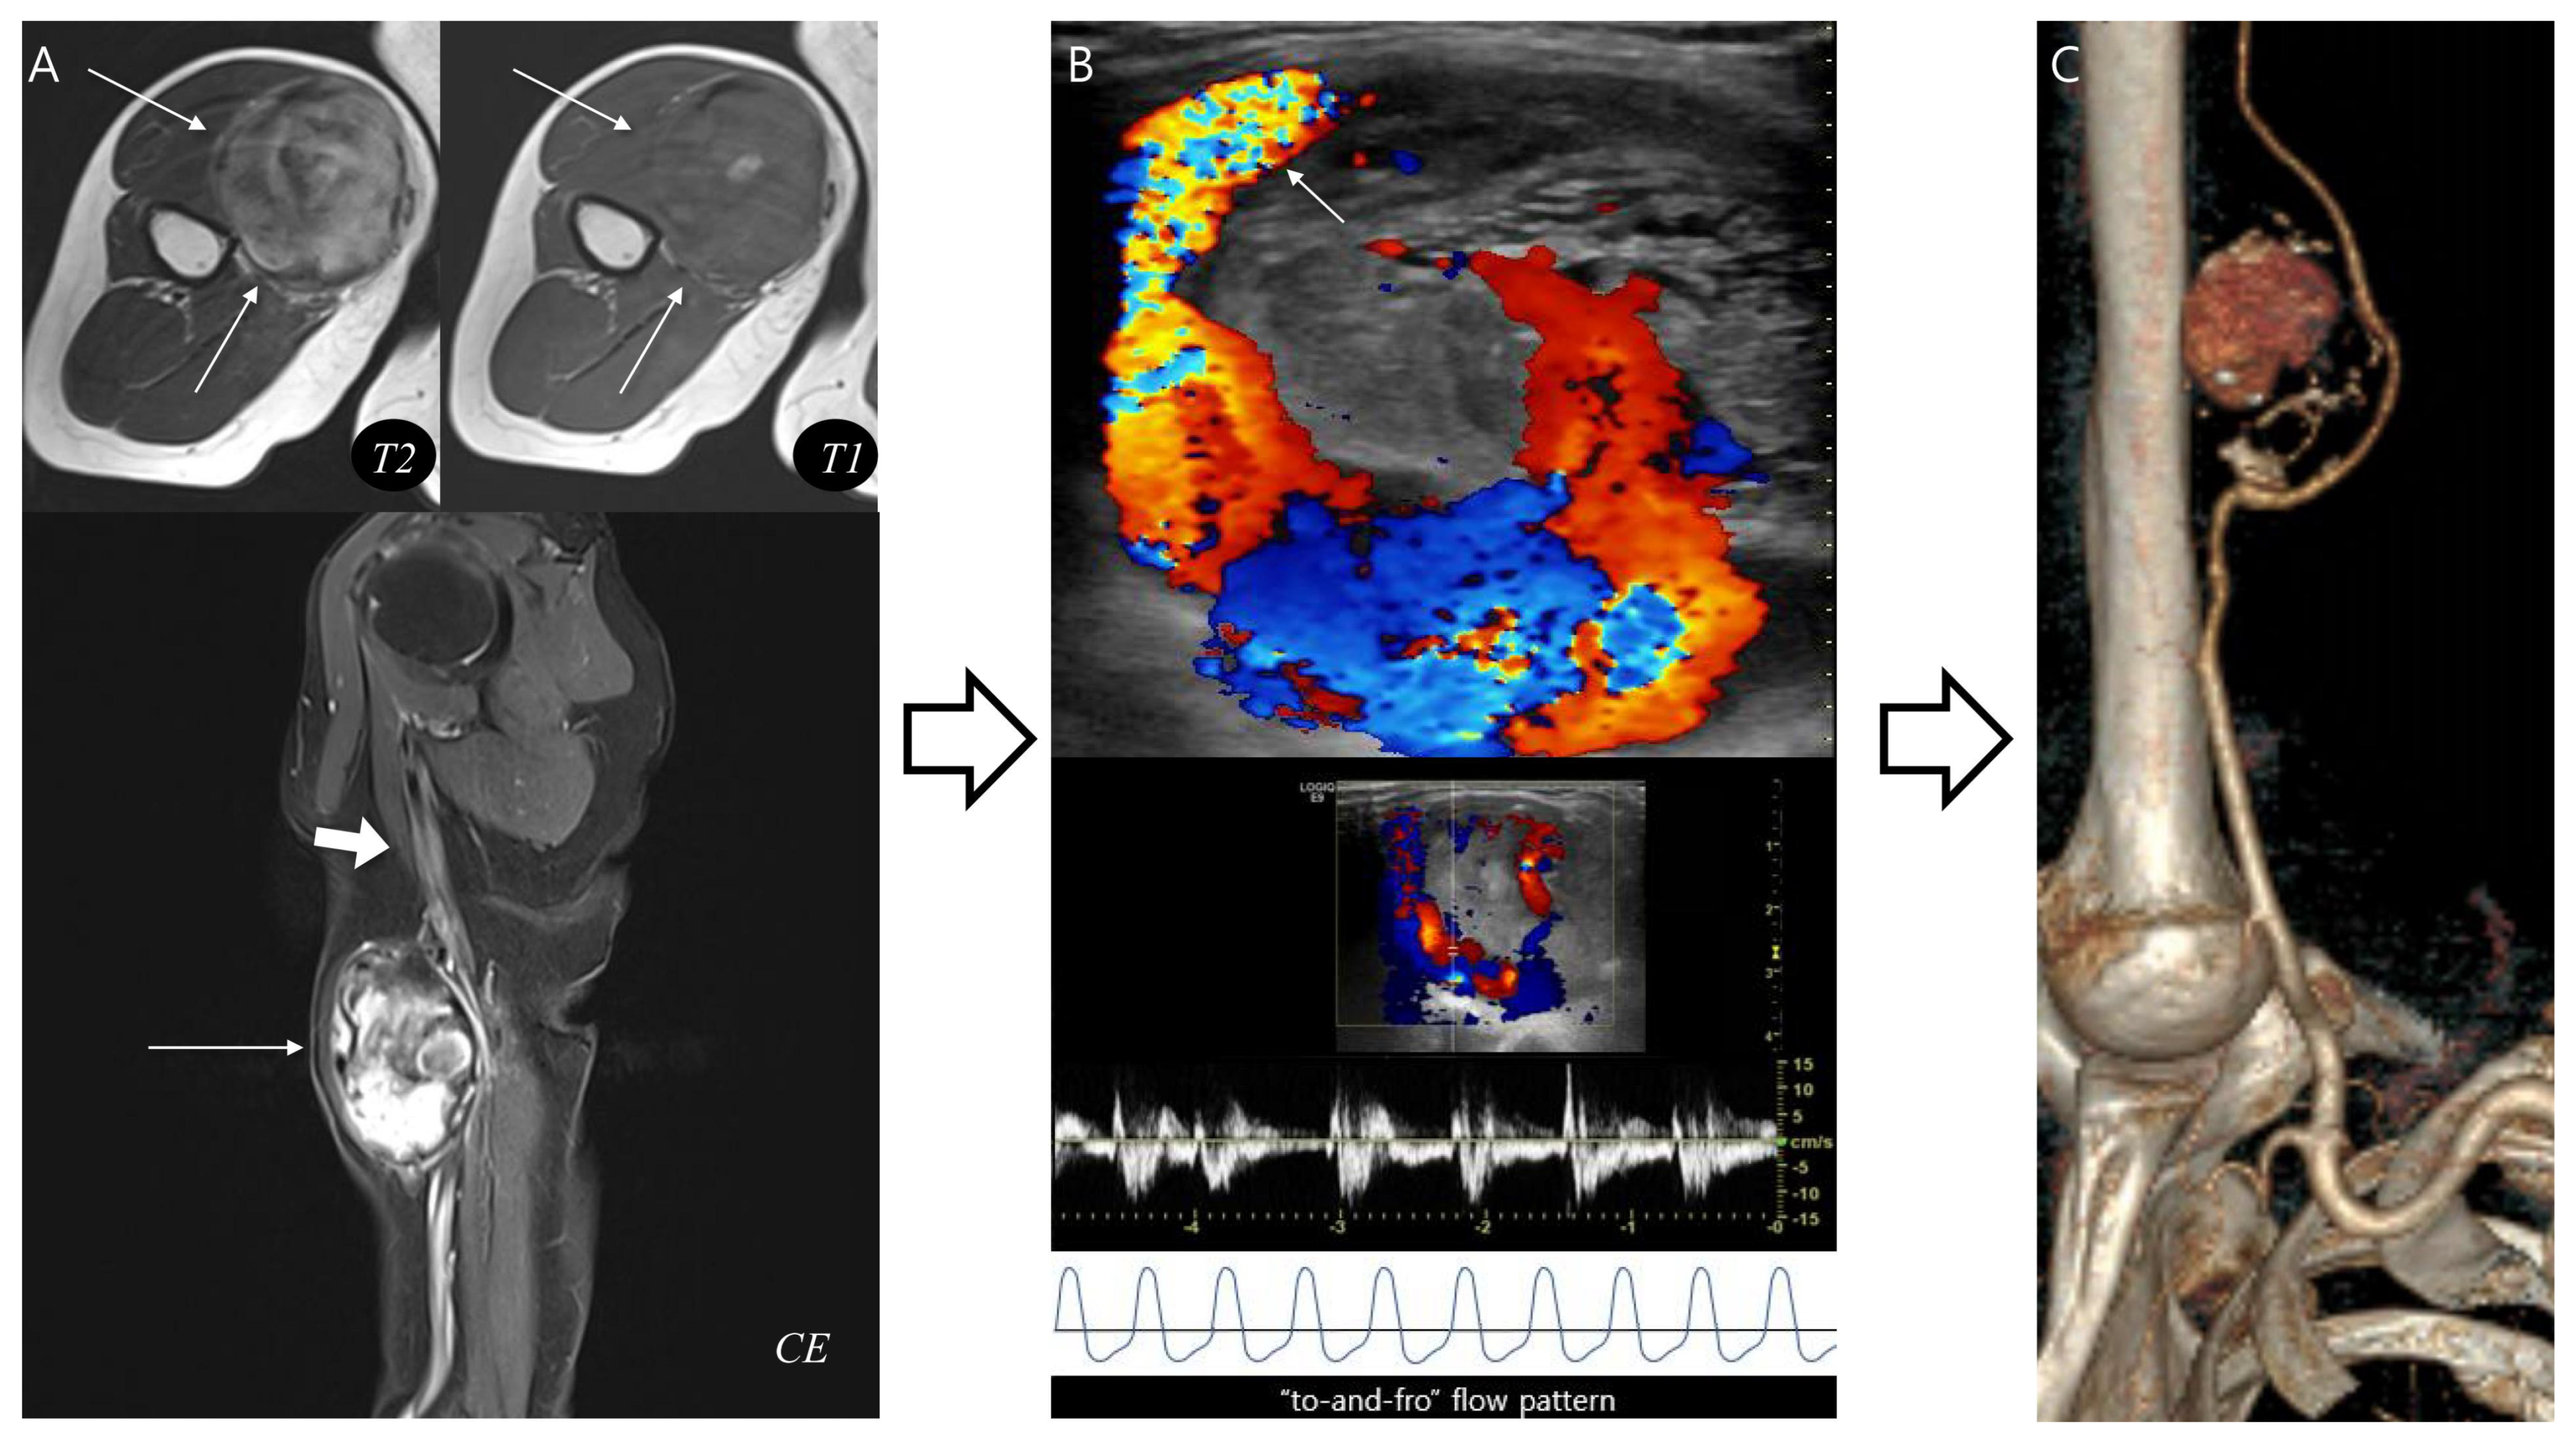

Second, the following MRI features were assessed—including lesion morphology, internal characteristics, pulsatile artifact, and relationship to adjacent structures (Figure 1). Morphology was categorized as either ovoid or multilobular in contour. Internal characteristics related to hematoma were evaluated as follows: (1) outermost peripheral low SI on T1WI—indicating a fibrous pseudocapsule with hemosiderin or collagenous tissue [22,23]; (2) inner peripheral high SI on T1WI, located just inside the low-signal rim—reflecting mural thrombus with methemoglobin [11]; (3) central high SI on T1WI—consistent with subacute/mature methemoglobin or repetitive rebleeding deposits [24]; (4) central flow void on T1WI and T2WI, appearing as a distinct signal void or markedly hypointense core due to rapid intraluminal blood flow, observed on all sequences (but most conspicuous on T2WI due to strong flow-related dephasing)—indicative of fast-flow blood [25,26]; (5) septation—representing internal fibrous septa or loculations [5]; and (6) nodular enhancement—suggesting granulation tissue or neovascularization.

Figure 1.

MRI findings of pseudoaneurysm (A–C) and chronic expanding hematoma (D–F). (A) Axial T2-weighted and (B) T1-weighted images show an intramuscular, ovoid mass with a central flow void (asterisk in (A,B), fast-flow blood), pulsatile artifact (dotted arrow in (A,B) and inner peripheral high SI on T1-weighted image (arrows in (B), mural thrombus). (C) Coronal T2-weighted image demonstrates neurovascular involvement (arrowhead). (D) Axial T2-weighted and (E) T1-weighted images reveal a multilobular subcutaneous mass with heterogeneous signal intensity with septations (arrow in (D,E)). (F) Coronal T1-weighted contrast-enhanced image demonstrates nodular enhancement (arrowheads, granulation tissue) within the mass.

A pulsatile artifact (Figure 1) was defined as a motion-related imaging artifact on MRI that arises from the periodic pulsation of blood flow, typically appearing as ghosting of SI along the phase-encoding direction and was considered as an indirect marker of active vascular flow [27,28].

Last, neurovascular bundle involvement (Figure 1) was considered positive when displacement, encasement or infiltration of adjacent neurovascular structures was observed [29].